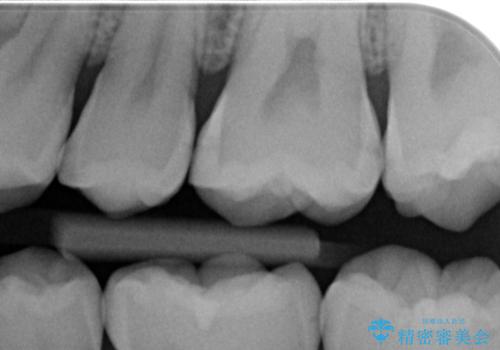

- 歯と歯の間に虫歯(コンタクトカリエス)が見られたので拡大鏡下で取り除き、e-maxインレーで治療を行いました。

歯と歯の間は歯ブラシでは磨けないので毎日フロスや歯間ブラシを使用する事が虫歯になるリスクを下げる事があります。